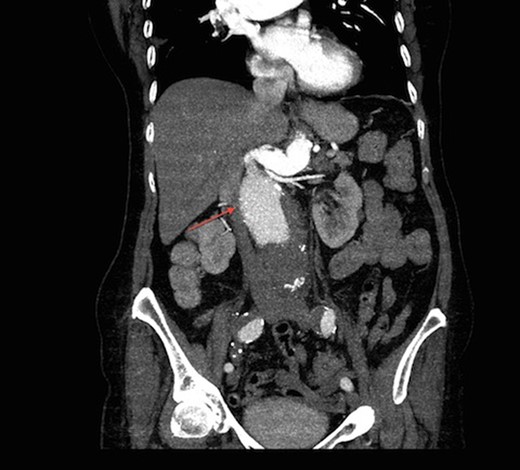

On arrival at our hospital, she was hemodynamically stable, with all vital signs within the normal range. Abdominal examination revealed a pulsating mass in the center of the abdomen. A computed tomography (CT) angiogram of aorta was performed for further evaluation that showed ectatic aorta from arch to the diaphragm. There was an 8.7-cm infra-abdominal AAA with extension into both common iliac arteries. The aneurysm neck was tortuous with an acute angle making endovascular repair challenging (Figs 1–4).

Three-dimensional construction of CT aortogram showing displaced and compressed IVC (asterisk) due to large AAA (arrow head).